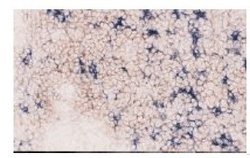

Immunohistochemistry

ABIN786618 IHC